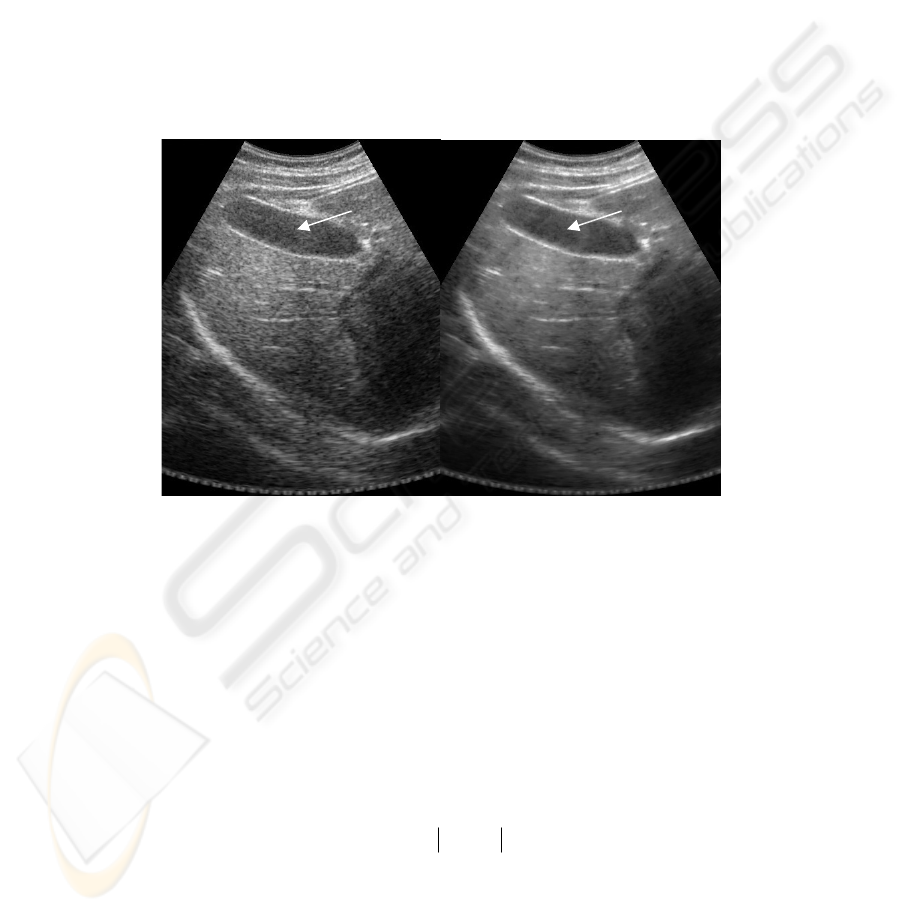

Thus, the microstructure of an image is determined by the scattering objects which

are smaller than “the resolution spot” of the acoustical system. An acoustical image of

such objects in principle does not have any geometric likeness with the original object

whereas within a single “resolution spot” there are tens and hundreds inhomogeneities

which are added statistically. As we deal here with the coherent adding of the acous-

tical oscillations, an interference amplification or weakening of the scattered signal

take place, which are not directly caused by the real changes of the reflective charac-

teristics of micro-objects (speckle-noise).